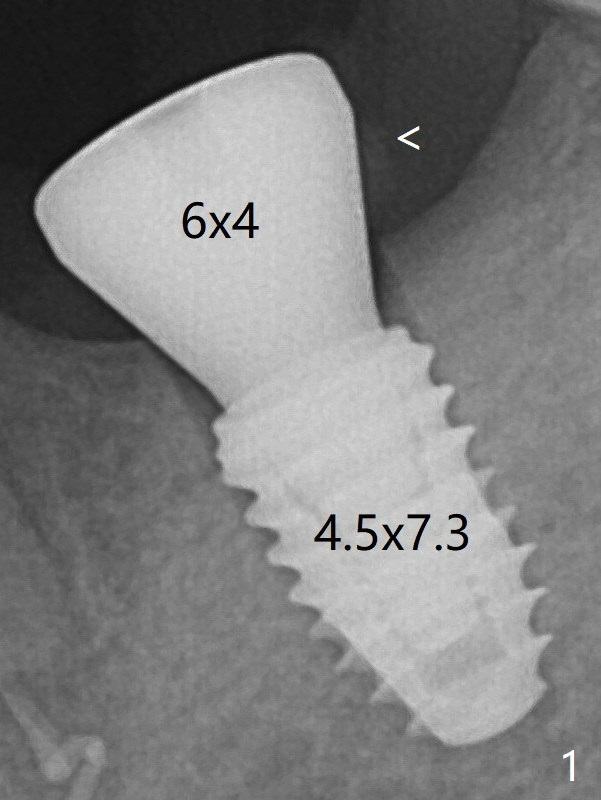

According to drill sequence at #19, the osteotomy is over prepared with the 4.5x8.5 mm last drill.  The bone density does not feel so high that warrants use of 5.0 mm cortical tap.  The insertion torque is ~ 25 Ncm (Fig.1).  When a 6x4 mm healing abutment is placed, the implant does not turn.  The distobuccal gingiva is slightly torn; following packing autogenous bone (<), periodontal dressing is applied.  A provisional is not fabricated at #19, considering short healing time (Fig.5).  But there is no gap between the implant  and surrounding bone, as compared to Fig.1.  It appears that overprep helps healing.